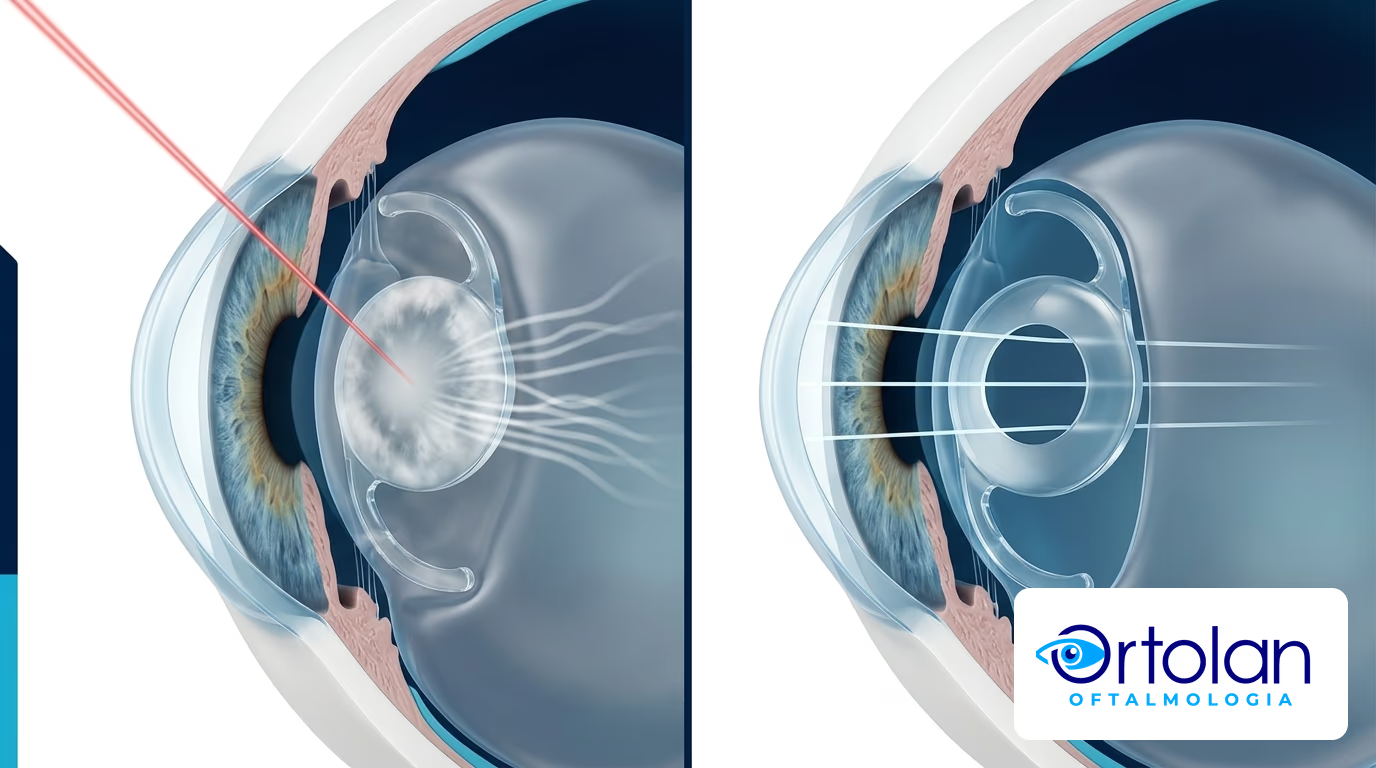

Não. Uma vez removido, o cristalino não volta a se opacificar, porque ele já não está mais no olho. O que pode acontecer, em alguns pacientes, é a opacificação da cápsula posterior. Essa membrana fina dá sustentação à lente intraocular e pode ficar turva com o tempo.

A solução costuma ser a capsulotomia YAG, um procedimento ambulatorial de alguns minutos, indolor e sem cortes. O laser cria uma pequena abertura central na cápsula, e a visão geralmente melhora rapidamente.